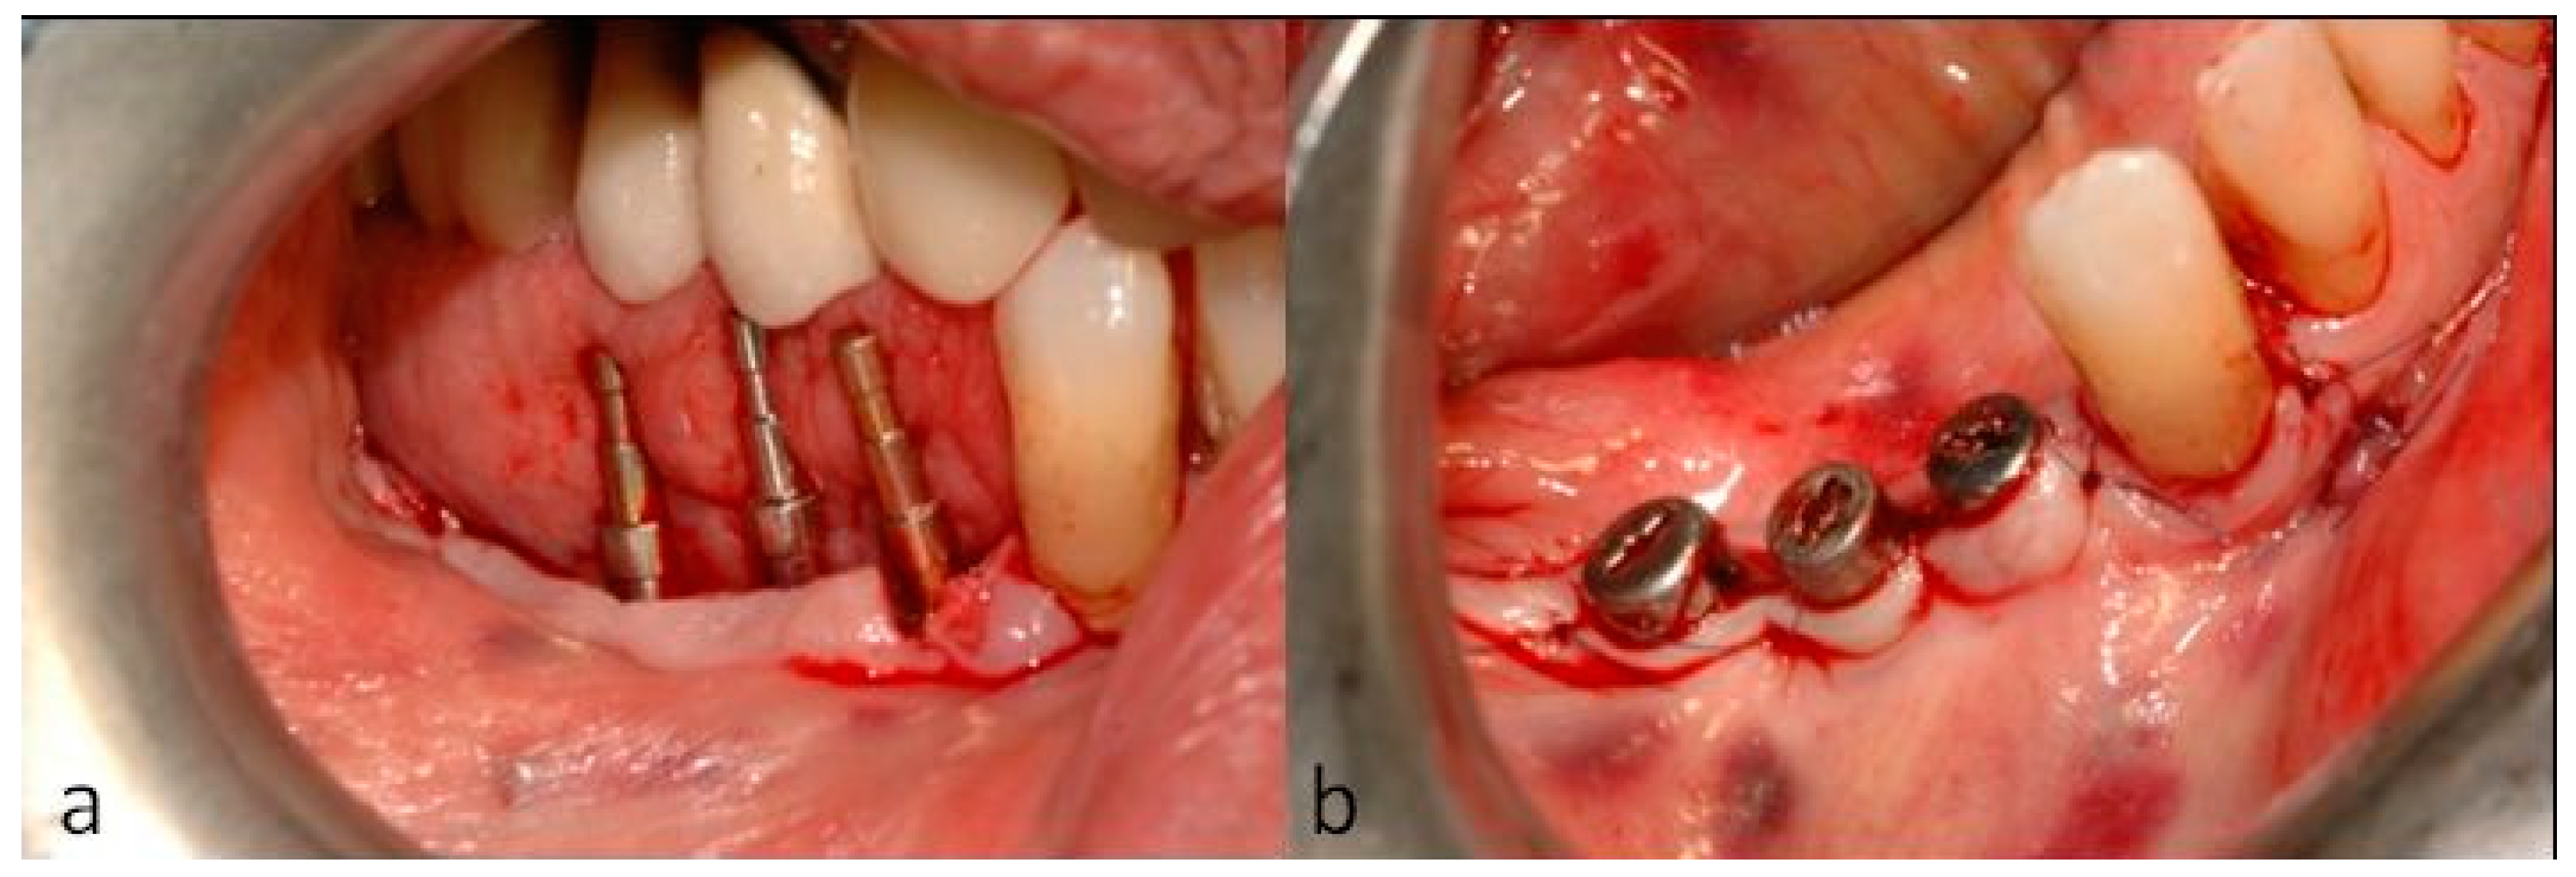

2. Case Description